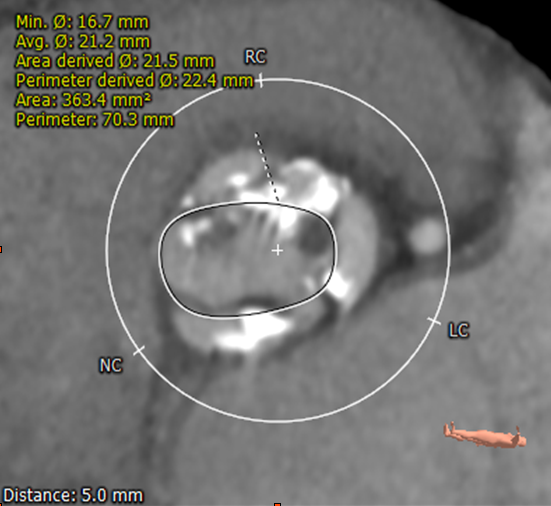

术后即刻超声评估显示峰值流速2.1m/s,平均压差8mmHg,瓣口面积约2.1cm²,瓣膜定位精准,形态良好,无冠脉堵塞,无房室传导阻滞,无瓣周漏,血流动力学指标理想,手术圆满完成。

术后总结

本例患者双侧冠脉堵塞高风险,中山团队为避免冠脉阻塞,在瓣膜选择上打破既往的常规,downsize一个型号且减容量2ml释放,体现了团队对TAVR技术的深厚理解。

术中选择纽脉医疗TAV-23mm Prizvalve®球扩瓣,既避免了冠脉阻塞、瓣周漏,又防止了房室传导阻滞的发生,给患者提供了最佳的治疗,同时展示了Prizvalve®瓣膜系统在本例高冠脉堵塞风险患者临床应用的安全性和有效性。